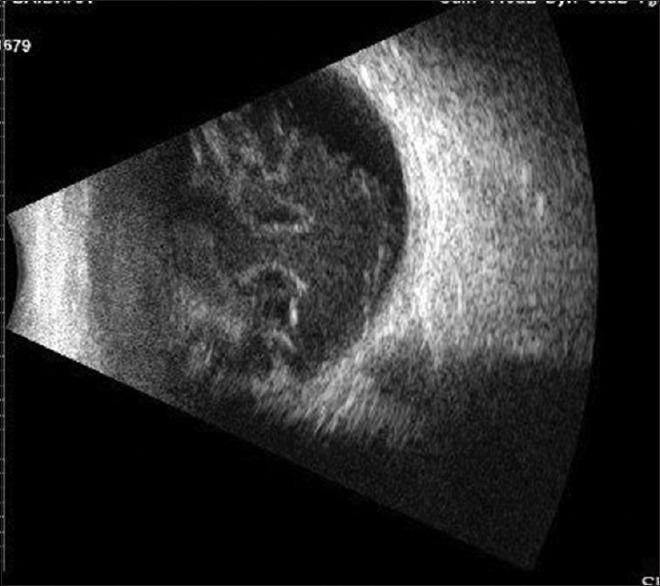

Scleral rupture is a rare but significant complication that can occur due to multiple risk factors. In this report, we discuss two instances of scleral perforation that happened during a silicone oil injection and after a peribulbar injection. Our study suggests that prior ocular surgery is a further risk factor for intraoperative scleral rupture, and more investigation is required to identify additional relevant risk factors that weaken the sclera.